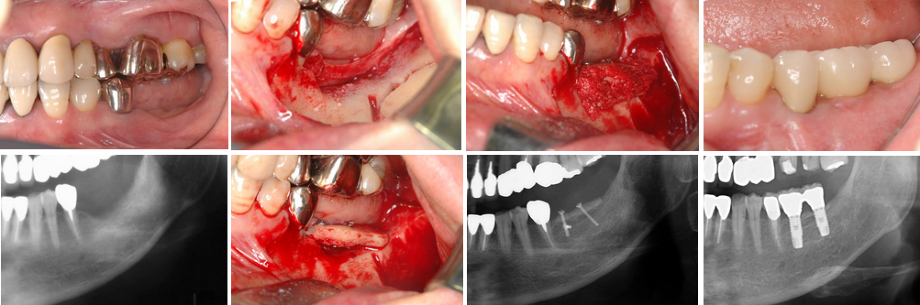

3.極度の骨・軟組織欠損がある2歯欠損症例(症例 5、自家骨移植と有茎口蓋弁移植)

極度の骨欠損があったが、オトガイ部から10mmの厚みの皮質海綿ブロック骨移植にて審美的インプラント治療を行いました。歯肉の厚みを増やすために有茎口蓋弁移植も併用しました。

4.極度の骨・軟組織欠損がある2歯欠損症例

(他院でトラブルとなった症例 2の再インプラント治療、自家骨移植と有茎口蓋弁移植)

まず予後不良インプラント撤去し、極度の骨欠損があったが、オトガイ部から10mmの厚みの皮質海綿ブロック骨移植にて審美的インプラント治療を行いました。歯肉の厚みを増やすために有茎口蓋弁移植も併用しました。